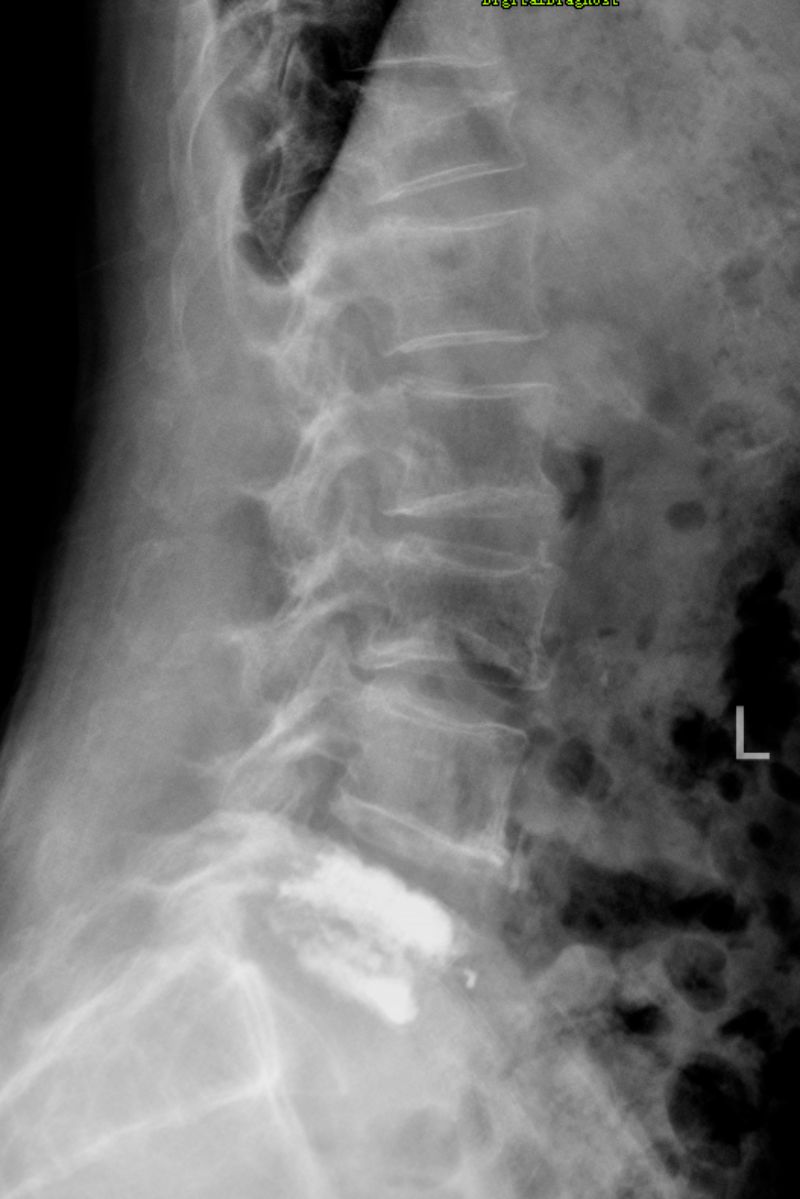

69歲的梁叔,過去兩年多經常有腰疼,自己吃點藥就熬過去了,2個多月來腰疼比之前還嚴重,并且伴隨有左腿疼痛、麻木,嚴重時甚至無法走路,在其他醫院住院理療后效果欠佳,到我院脊柱外科住院治療。住院后完善檢查,發現梁叔是腰椎間盤突出癥,腰5/骶1節段甚至有部分椎間盤髓核脫出壓迫神經,造成梁叔如此劇烈的腰腿痛癥狀,不手術摘除椎間盤進行減壓難以恢復。脊柱團隊對梁叔的病情進行深入討論研究,決定對梁叔實施UBE手術。UBE手術是在關節鏡輔助下,經過擴大椎間孔,摘除椎間盤髓核,對神經進行減壓,創傷小,術中出血少,僅有2個約1厘米的刀口,術后第二天即可下地行走。飽受病痛折磨的梁叔聽說是做微創手術后,毅然決定手術。因梁叔年級較大,并且有慢性阻塞性肺病、肺氣腫、慢性胃炎的病史,姚仕奮聯系了麻醉科團隊,為其制定了適宜的麻醉方案,于2023年11月06日,在麻醉團隊的保駕護航下,脊柱團隊為梁叔施行了UBE手術治療,術后梁叔馬上感覺腰腿痛癥狀明顯好轉,術后第1天,佩戴支具的梁叔就可以自行下地行走了。

開科1個月以來,我院脊柱外科已施行椎間孔鏡、UBE微創手術10臺,減少手術創傷歷來是外科醫生的追求,“微創”則是在當今醫學發展最具有人性化的先進手術理念,與以往常規手術相比,微創技術是以最小的創傷解決患者的病痛。由于微創手術創傷小,患者遭受痛苦少,身體的損傷輕,康復速度快,有效減少或避免了傳統手術給患者留下的創傷、合并癥。我院脊柱外科可施行椎間孔鏡下椎間盤髓核摘除、UBE減壓、UBE融合等微創手術,可更好、更微創的為群眾服務。